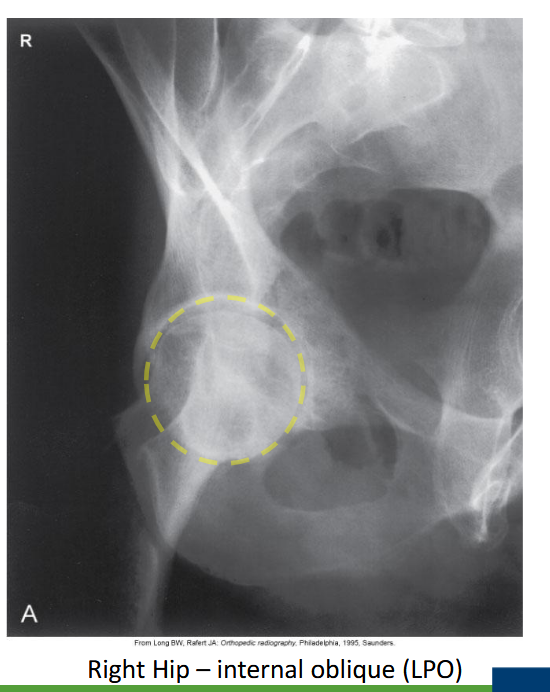

What are Judet views used for?

Evaluation of acetabular fractures.

<p>Evaluation of acetabular fractures.</p>

Which acetabular rim does the internal oblique Judet view show?

Posterior rim. (SHOWN #2 PURPLE)

<p>Posterior rim. (SHOWN #2 PURPLE)</p>

Anterior column. (SHOWN #1 RED)

<p>Anterior column. (SHOWN #1 RED)</p>

What is the degree of obliquity for Judet views?

45°.

What is the patient position for an internal oblique Judet view?

Affected side raised 45°.

<p>Affected side raised 45°.</p>

Where is the CR for a bilateral Judet view?

2.5 cm medial & inferior to the raised ASIS.

Where is the CR for a unilateral internal Judet view?

5 cm inferior to the raised ASIS.

Which oblique Judet view produces an 'O'-shaped acetabulum?

Internal oblique.

<p>Internal oblique.</p>

What does the iliopubic line represent in Judet views?

Anterior column.(SHOWN #1 RED)

<p>Anterior column.(SHOWN #1 RED)</p>

What does the ilioischial line represent in Judet views?

Posterior column.(SHOWN #1, ORANGE)

<p>Posterior column.(SHOWN #1, ORANGE)</p>

What does minimal overlap at the pubic symphysis indicate in Judet views?

Correct positioning.

Which Judet view shows the obturator foramen widest?

Why are Judet views performed in trauma cases?

To assess column involvement in acetabular fractures.